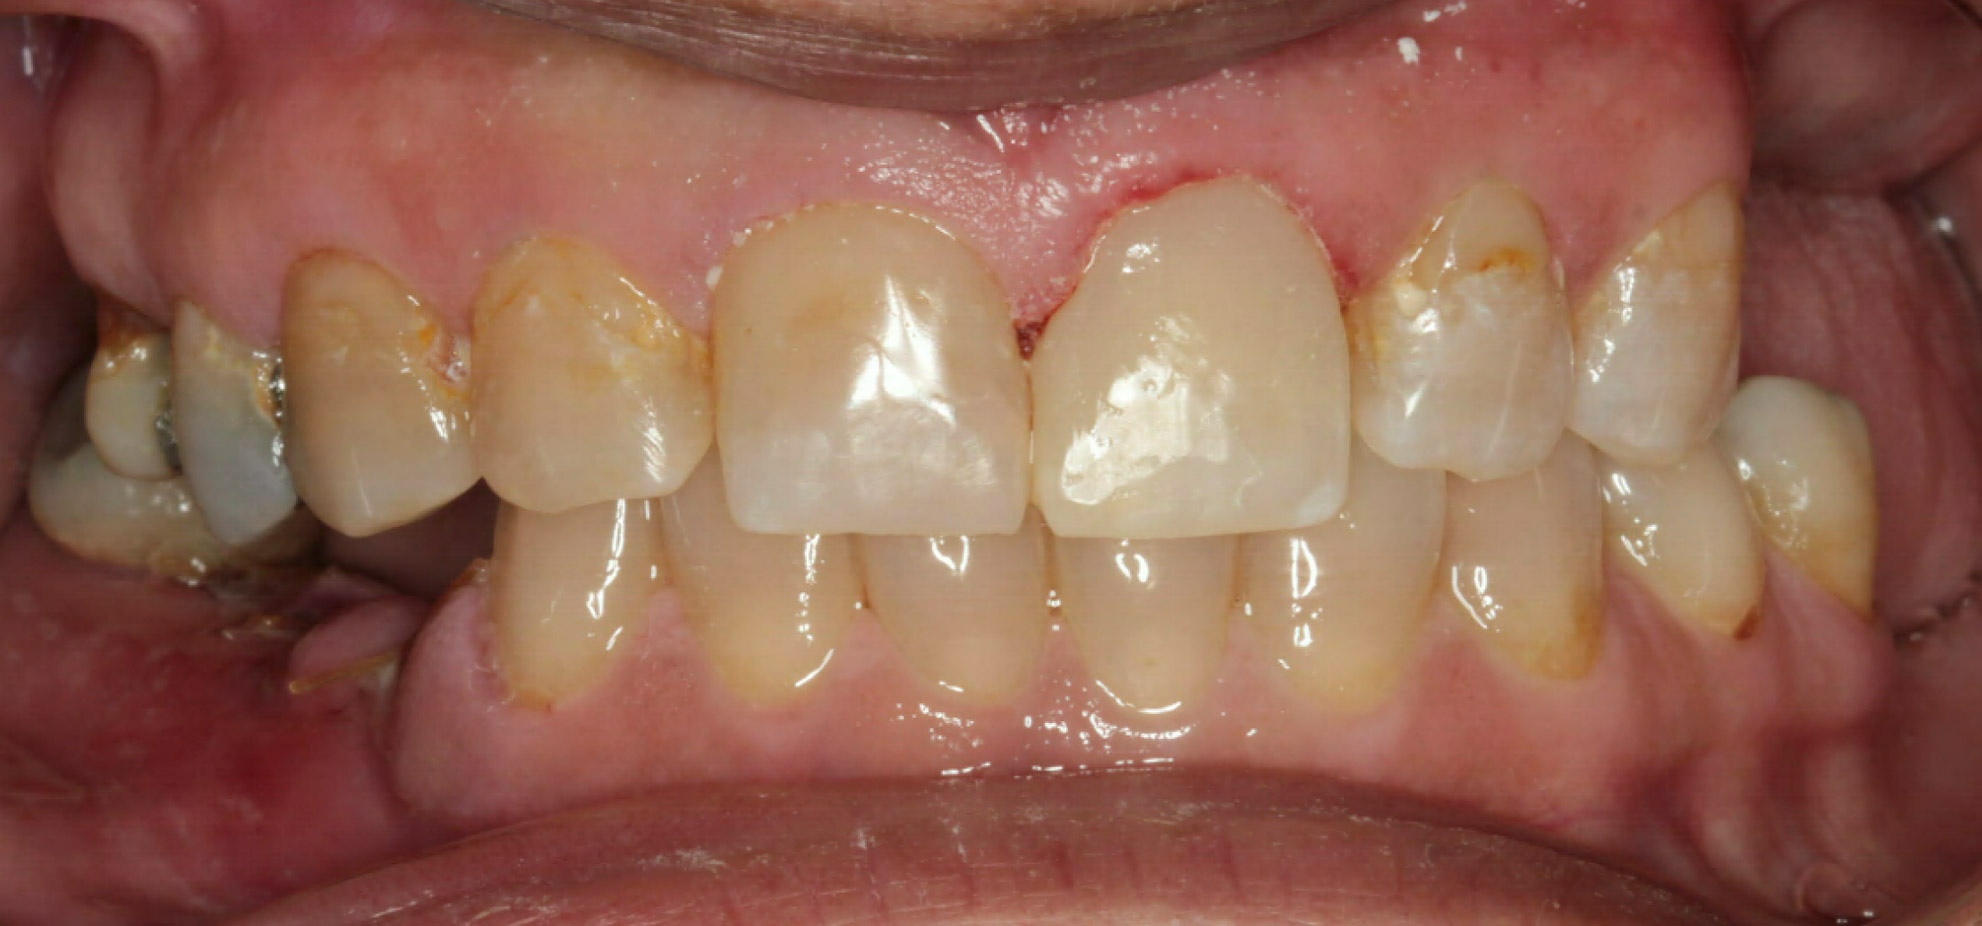

Intra Oral Pictures (3)

(Treatment in progress)

Intra Oral Pictures (4)